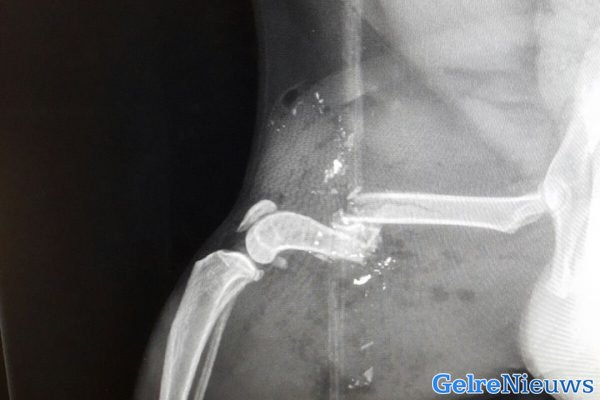

Het gebeurde vermoedelijk maandagavond tussen 18:30 en 22:30 uur in de omgeving van de Heumensebaan in Groesbeek door een nog onbekend persoon. Het kogeltje is dwars door de voorpoot gegaan en in de buik van de kat terecht gekomen. De poot van de kat Jackson is er zo slecht aan toe dat deze vermoedelijk geamputeerd moet worden.